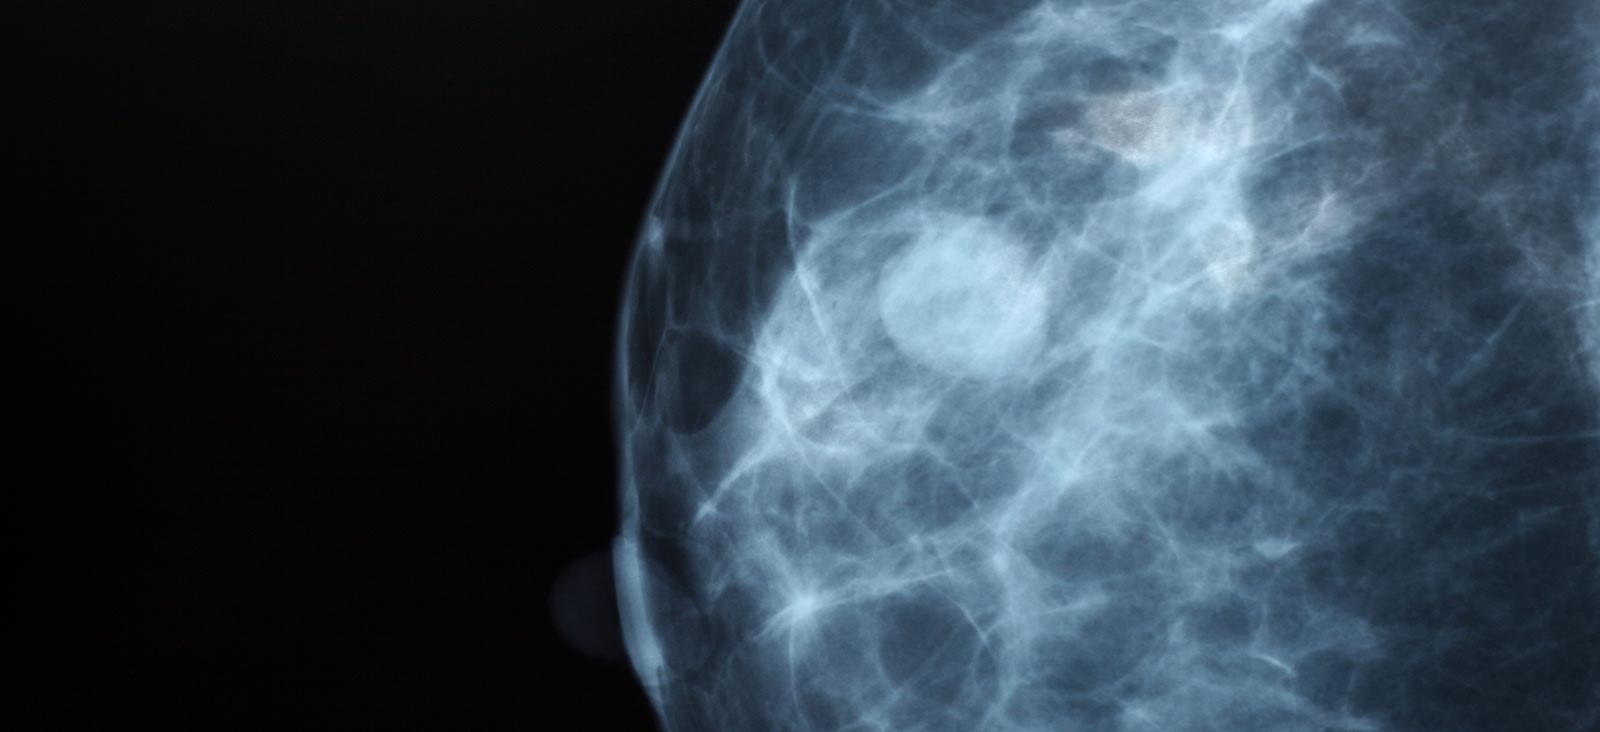

Imaging to show different densities in breast tissue

These X-ray scans show the four categories of breast density. The two images on the left are considered “not dense,” and the two on the right are considered “dense.”